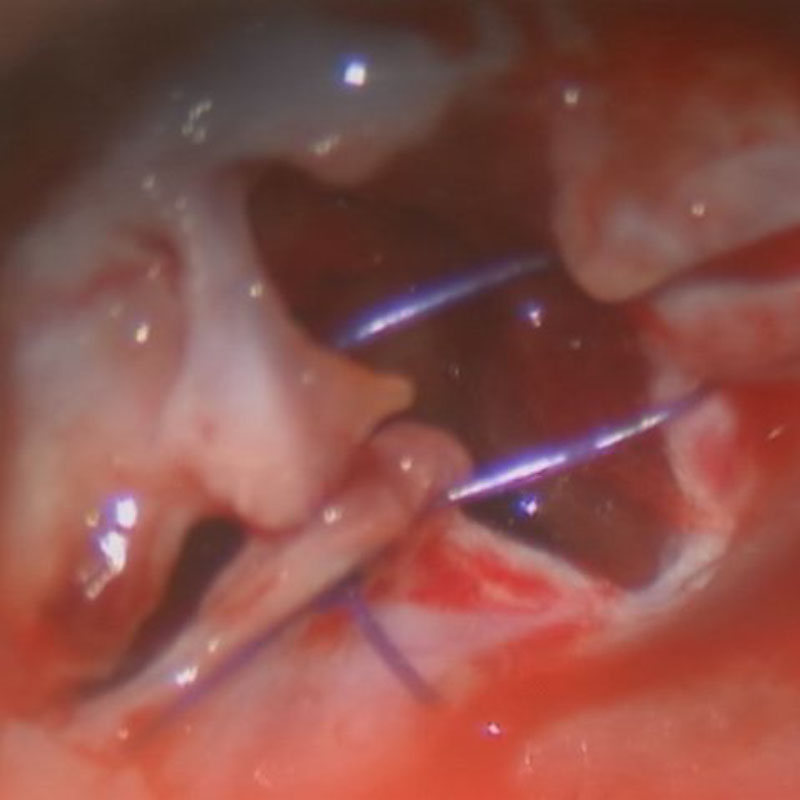

517

'24年3月

10代

小脳血管芽腫

頭蓋内腫瘍摘出術

No.’24_19 手術前1

No.’24_19 手術前2

No.’24_19 摘出 前

No.’24_19  摘出 中

No.’24_19 摘出 後